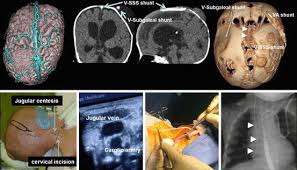

Complex Hydrocephalus Management By Smart Shunt Springerlink